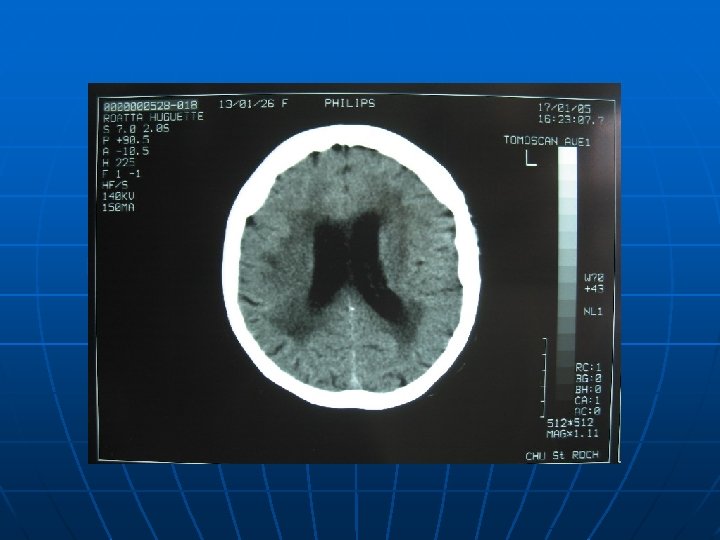

Exemple clinique: un cas dans le service n n n Femme 79 ans ATCD: • HTA • Obésité • Artériopathie carotide • 4 verres alcool par jour Motif d’hospitalisation: Méningite à pneumocoque n Ttt en cours : Captopril 50*3 Alpress 5*2 Kardégic 75 Au S. A. U st Roch TA: 13/7 FC: 105 T°: 39 SATO 2: 98% à 6 L ph: 8 pco 2: 39 po 2: 99. 2 hco 3: 25. 1 GB: 15000 CRP: 116 Patiente amenée par le SMUR Antibes pour suspicion d’AVC. -Scanner cérébral sans produit de contraste: absence d’hémorragie méningée. -PL confirmant le diagnostique de méningite à pneumocoque -transfert en réa archet

C/Examen Paraclinique: n 1/Ponction lombaire: clé du diagnostic, avant tout autre examen: • Analyse du LCR: n n trouble hypercellularité(>10/mm 3) avec prédominance de PNN Hypoglycorachie: 0. 35 -0. 52 g/l Hyperprotéinorachie: 0. 4 -0. 45 g/l • On effectue: n Coloration gram: • +=pneumocoque ou lysteria • - =méningocoques, E. coli et H; influenzae • Suivie d’examen direct, culture et ATBgramme • Selon les circonstances: recherche antigènes solubles et PCR. n 2/Scanner: si signes neuros focaux ou suspicion de complication intra-crânienne(HTIC)